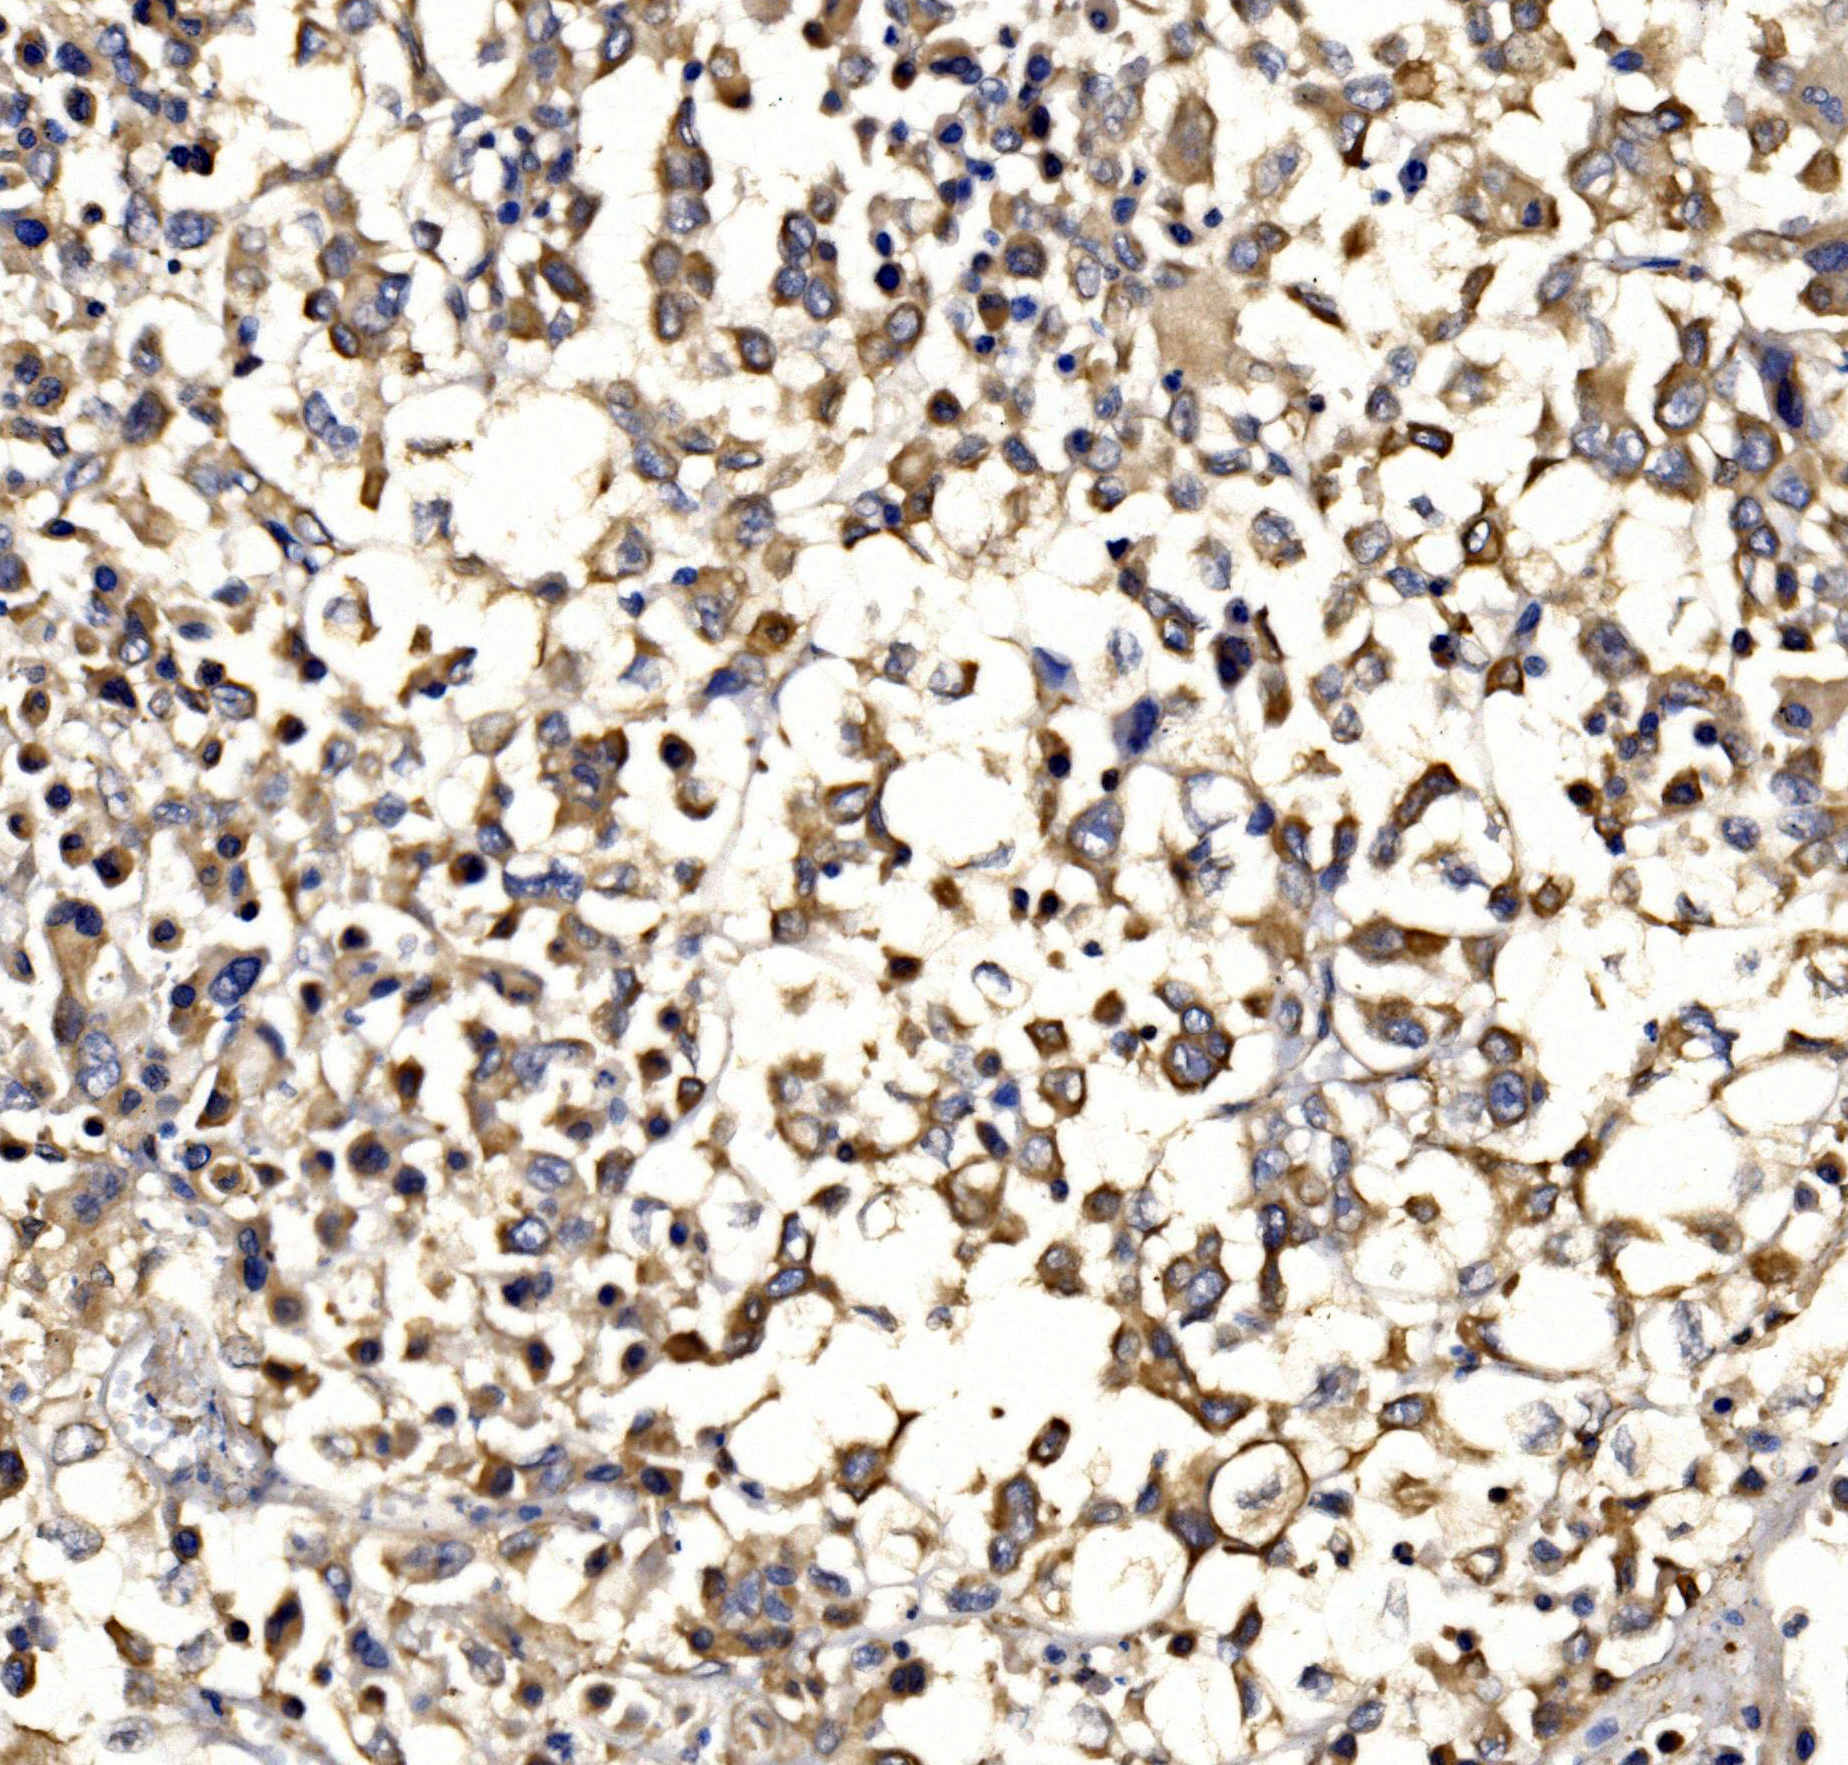

IHC analysis of EPAC1/RAPGEF3 using anti-EPAC1/RAPGEF3 antibody (A02483-3).

EPAC1/RAPGEF3 was detected in a paraffin-embedded section of human pancreatic cancer tissue. Biotinylated goat anti-rabbit IgG was used as secondary antibody. The tissue section was incubated with rabbit anti-EPAC1/RAPGEF3 Antibody (A02483-3) at a dilution of 1:200 and developed using Strepavidin-Biotin-Complex (SABC) (Catalog # SA1022) with DAB (Catalog # AR1027) as the chromogen.